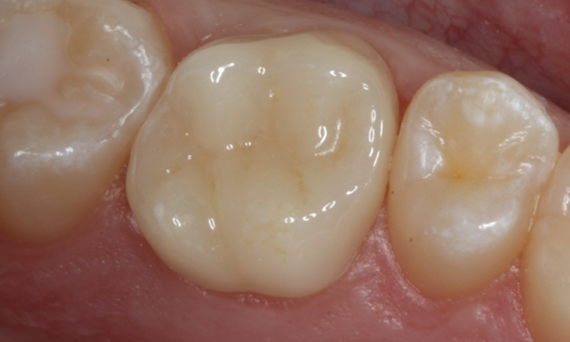

Primer molar superior en 60 minutos

Corona individual IPS.emax CAD

El caso clínico demuestra la rapidez y eficiencia con la que CEREC Primemill permite fabricar una corona de vitrocerámica de superficie completa chairside en una sola sesión, al mismo tiempo que cumple con las demandas estéticas más altas.

Antes: Insuficiencia grande del relleno de composite en el diente 16 con grietas marginales distales en la cresta, una grieta en la pared lingual y caries recurrente distal.

Después: Corona de vitrocerámica de superficie completa altamente estética.